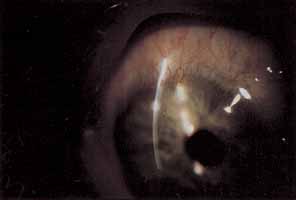

SUPERFICIAL NEOVASCULARIZATION

Superficial corneal neovascularization is a response to persistent hypoxia secondary to contact lens wear (Fig. 3).9,101–103 Rigid lenses rarely develop limbal hyperemia greater than normal controls. Daily wear–lens patients will often show an apparent increase in limbal vascularization, which actually represents limbal capillary dilation and rarely progresses to frank neovascularization. Extended-wear soft contact lens wearers most often exhibit significant limbal new vessel growth. Topical nonsteroidal antiinflammatory agents may suppress neovascularization, but their use has not become routine.104 Most often treatment consists of changing from extended to daily wear schedules, fitting with higher dK or thinner lenses or fitting with a looser soft lens. The use of soft extended wear lenses after penetrating keratoplasty is particularly risky because of the rapid neovascular response observed.105

Fig. 3 Severe superficial corneal neovascularization.